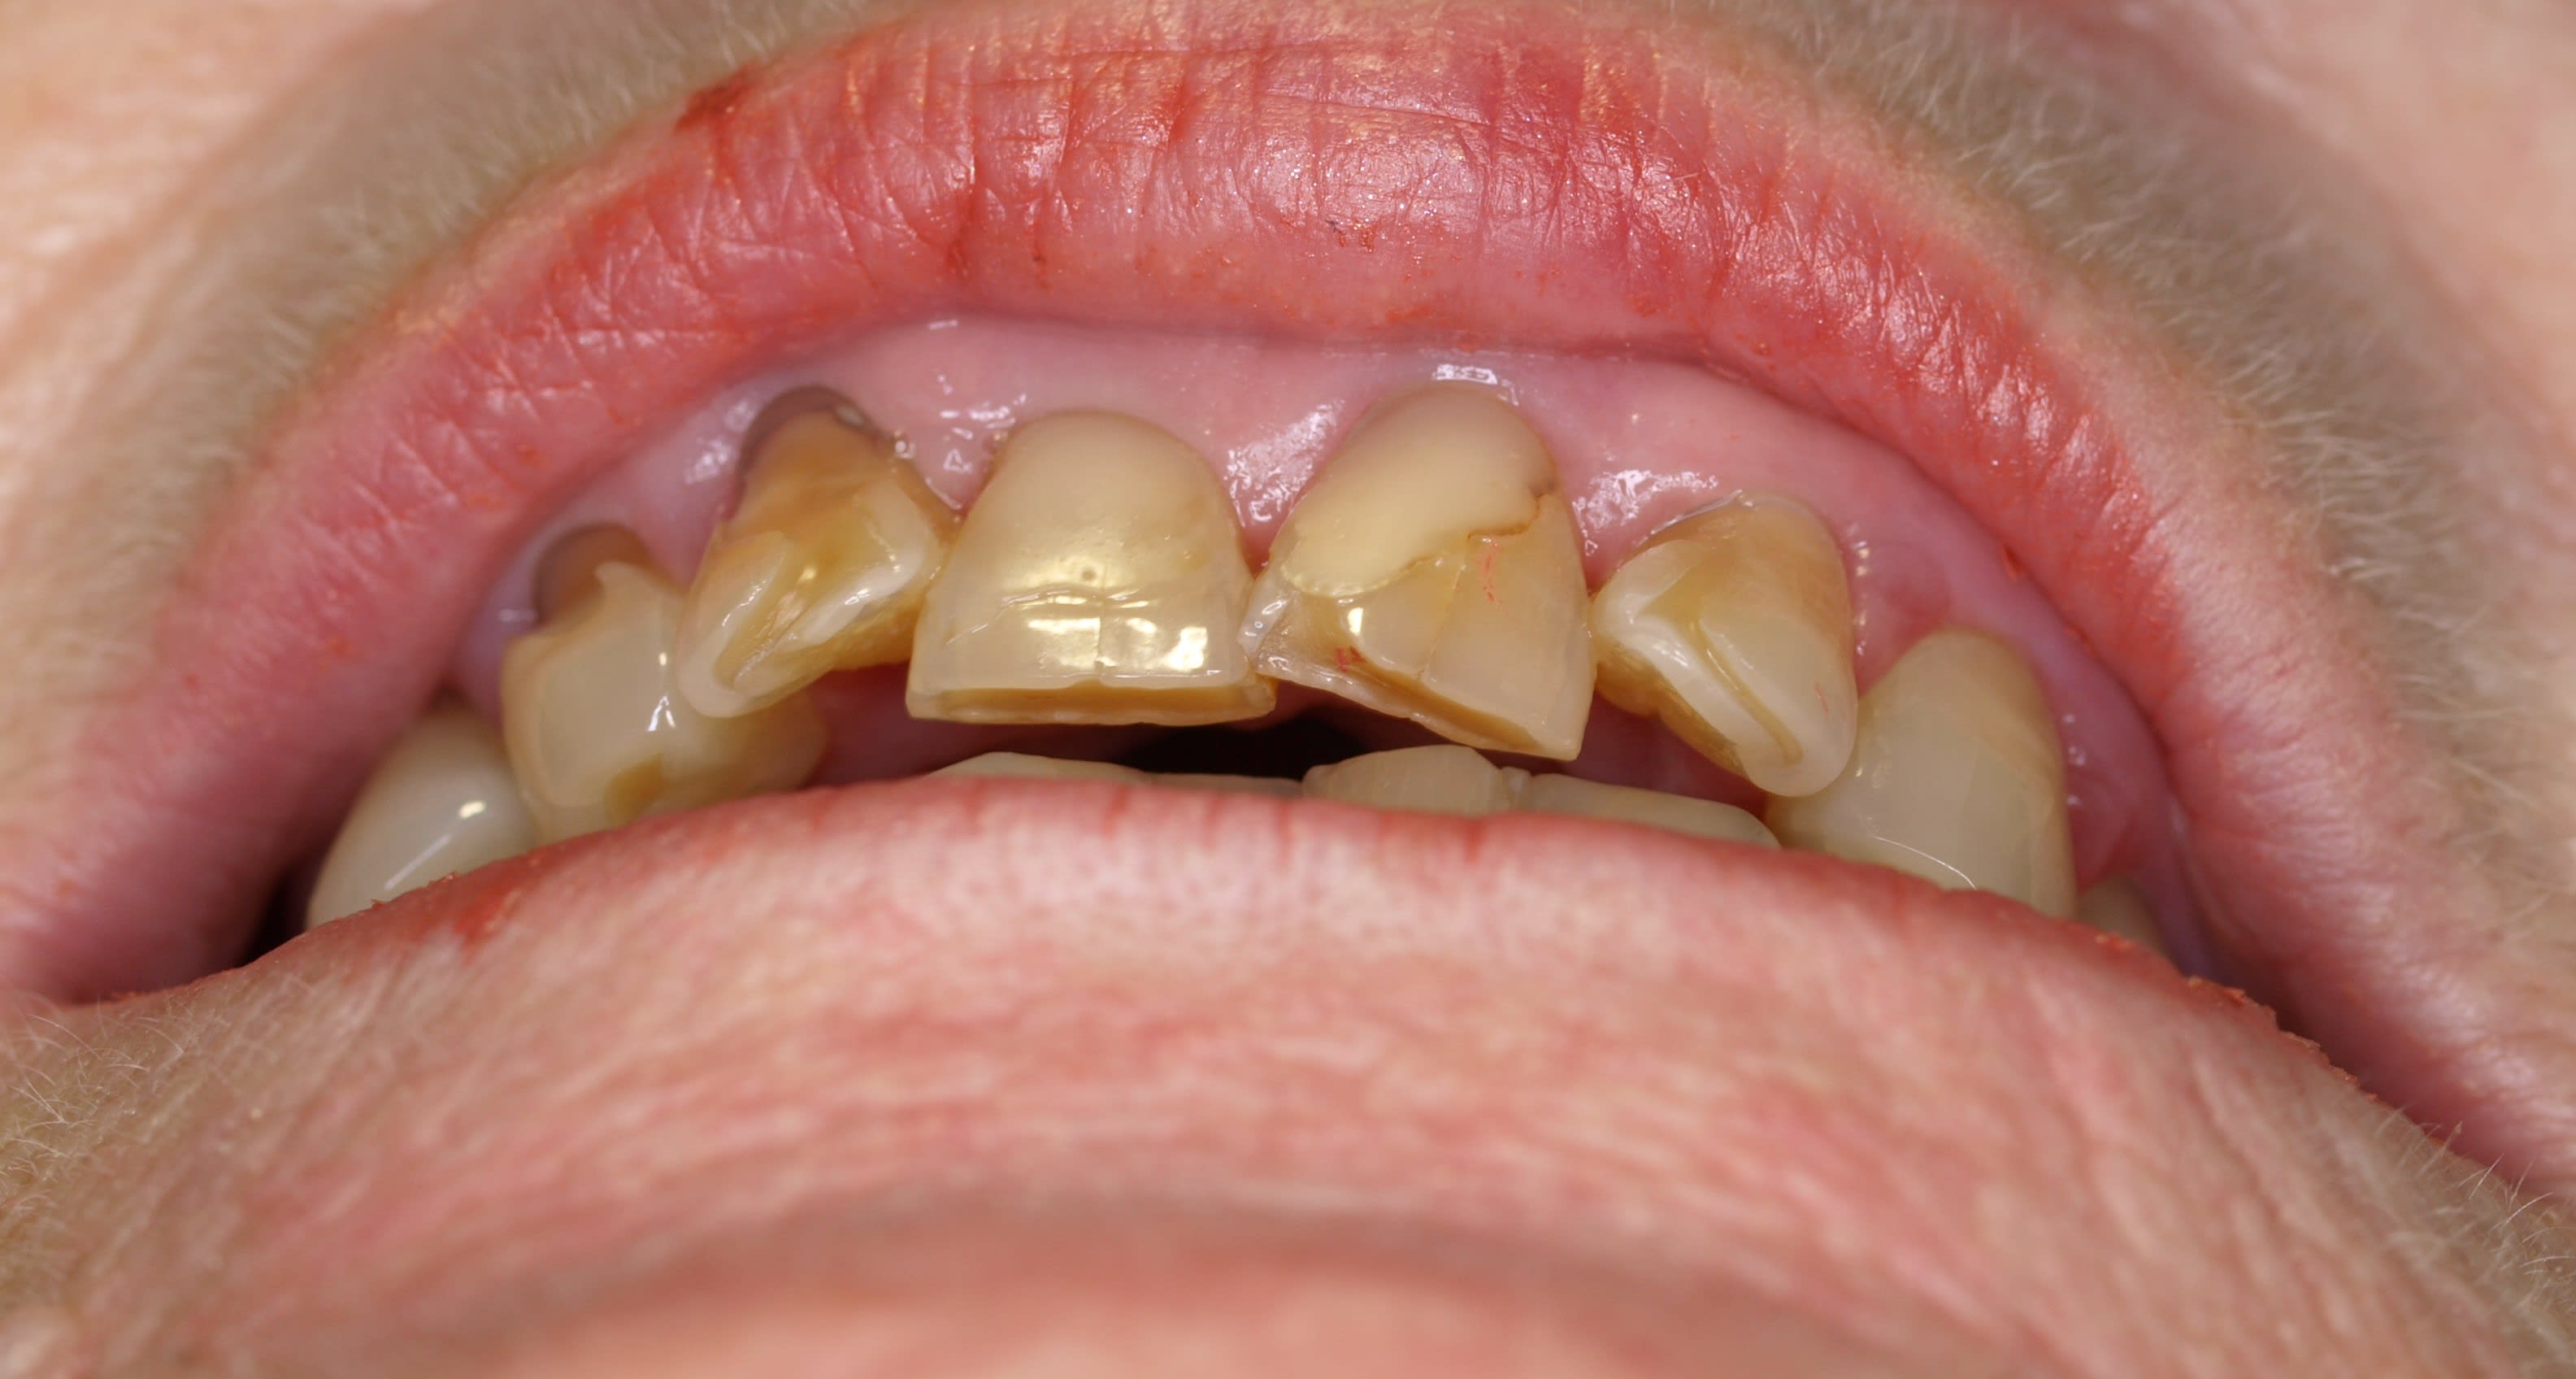

alors on dit que s il n y a pas beaucoup d os en vest la gencive remonte .

certes , mais si on diminuait le bombé racinaire ? , la distance projetée entre l os mesial et distal serait plus courte , et donc la gencive pourrait être plus épaisse puisque plus de place et moins tendue . pourquoi pas ?

et l idée c etait que j allais faire tout ce mezo mezo mi gratage radiculaire mi gratage osseux , non pas au hasard mais en fonction de l objectif esthétique final .

et pour ça on allait se le faire provisoires en place en intrasulculaire (pour l os et les racines) .

et même temps combler à la résine pour modifier les prov .

c était ça l idée :-)

ce qui m a donné ça .

qu' on soit bien d accord , ce sont les memes prov que la photo d avant , hein .

de souvenir je ne les avais même pas enlevés .